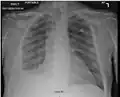

Complicated silicosis

Silicosis ILO Classification 2-2 R-R